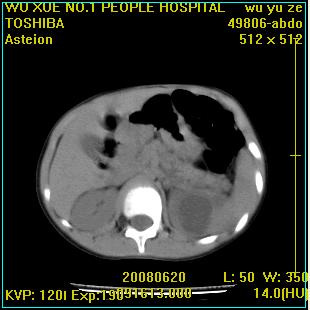

标题: PED0851:患儿,7岁,左腰部外伤一天,伴大量肉眼血尿。 [打印本页]

标题: PED0851:患儿,7岁,左腰部外伤一天,伴大量肉眼血尿。

左侧输尿管中段狭窄伴输尿管肾积水,考虑先天性狭窄可能性大.

左肾重度积水,原因不明;不排除左输尿管上段迷走血压迫或先天性狭窄所致可能。

左肾积水,输尿管上段扩张.考虑左输尿管下段狭窄受阻.

支持左肾积水,输尿管上段扩张.考虑左输尿管下段狭窄受阻

左肾重度积水

支持左肾积水,输尿管上段扩张.考虑左输尿管下段狭窄受阻。